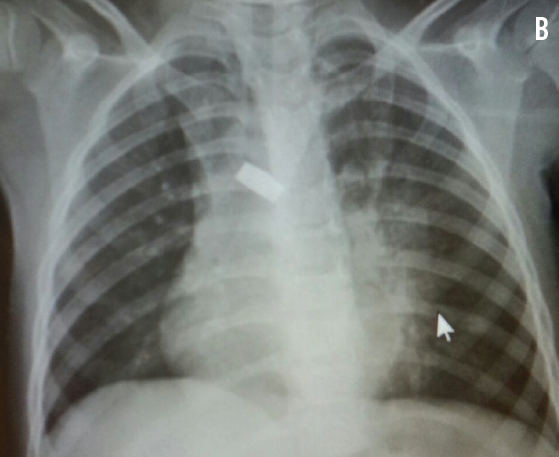

Physical examination findings were unremarkable except for the presence of mild respiratory distress, subcostal retractions, and expiratory wheezes.